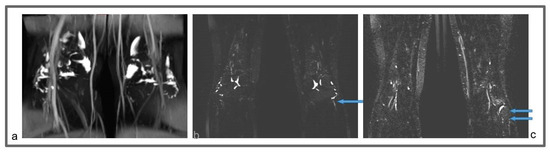

Figure 6.

Patient 3: Preoperative non-contrast MR lymphography (a) and at 1-year follow-up (b), based on high-resolution, heavily T2-weighted coronal sequences (turbo spin echo with repetition time 2870 ms, echo time 797 ms, field of view 380 × 380 mm, matrix 358 × 384, slice thickness 1 mm). The patient suffered from a marked increase in the size of the left ankle and distal leg, due to a large amount of epifascial fluid (a; blue arrows). The follow-up demonstrates a marked reduction in the epifascial fluid with a significant size reduction of the affected areas (b; blue arrows).

Figure 7.

Patient 3: Follow-up MR lymphography showing lymph nodes transplanted in the popliteal fossa (blue arrows) and coronal reconstruction of a 3D short-time inversion recovery (STIR) with repetition time 3000 ms, echo time 254 ms, inversion time 160 m, field of view 460 × 504 mm, matrix 315 × 384, slice thickness 1 mm.